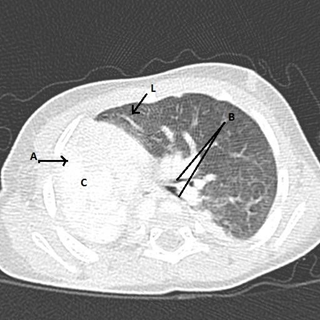

At the age of three weeks, a water soluble upper gastrointestinal contrast study revealed a mild stricture at 13 cms. It was dilated endoscopically at the age of two months and three months. The follow up contrast study at five months of age revealed normal esophageal lumen. However there was a smooth compression externally on the posterior aspect of the esophagus, below the level of the carina. A computer tomography (CT) and a CT angiogram confirmed the agenesis of the Rt. lung, absence of Rt. pulmonary artery and dextraposition of the heart with displaced mediastinal structures while excluding a vascular ring (Figure 1.2 & 1.3).

Figure 1.2 CT chest (lung window).

A: absent Rt. Lung, B: Lt. upper and lower lobe bronchi, C: dextroposition of heart - displaced in to the Rt. Hemi thorax, L: hyperinflation of contra lateral lung